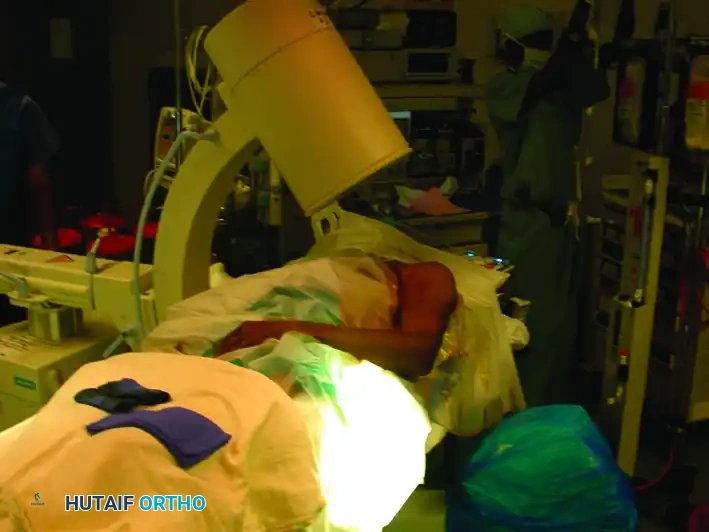

C-Arm Positioning

Place the image intensifier (C-arm) unit on the opposite side of the table from the surgeon. The monitor should be placed at the foot of the bed or across from the surgeon for direct line-of-sight.

The mobility of the C-arm is critical for obtaining orthogonal views without moving the patient's injured extremity:

* Anteroposterior (AP) View: Rolling the C-arm unit back away from the patient allows an adequate AP view of the shoulder and humerus.

* Lateral View: Rolling the unit forward over the patient allows an adequate lateral (scapular Y) view.

Image demonstrating the C-arm rolled back to obtain the Anteroposterior (AP) view.

Image demonstrating the C-arm rolled forward to obtain the Lateral view of the shoulder and humerus.

Composite view: Placement of the image intensifier for intramedullary nailing. Rolling the unit back allows the AP view, whereas rolling it forward allows the lateral view.